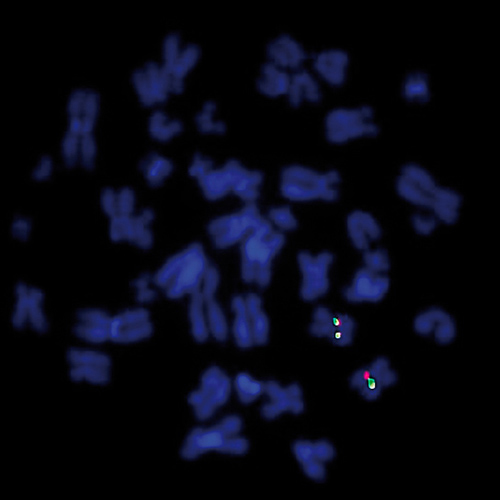

CCND1 (11q13) Break probe hybridized to a normal metaphase (2R2G).

Overexpression of the Cyclin D1 gene caused by amplification or translocation is described for several types of cancer. A t(11;14) is the main characteristic aberration in mantle cell lymphoma (documented in 40-70% of the cases. In MM, the same translocation t(11;14)(q13:q32) is the most common, with a reported frequency of 15% to 20% of the cases. Kreatech has developed this probe to detect rearrangements of the CCND1 gene region at 11q13 (KBI-10609) or for the translocation t(11;14) in Mantle Cell Lymphoma (KBI-10604) and for MM (KBI-10605). The CCND1 (11q13) Break FISH probe is optimized to detect translocations involving the CCND1 gene region at 11q13 in a dual-color, split assay on metaphase/interphase spreads.